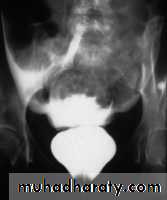

• Cystography is the best way of demonstrating the actual site of leakage from the bladder. If there is any suspecious associated urethral injury, an ascending urethrogram should be done first. There are two main types of bladder rupture:• Intraperitoneal rupture: caused by a direct blow to the distended bladder. Contrast introduced into the bladder will leak into the peritoneal cavity.

• Extraperitoneal rupture: may be part of an extensive injury such as occurs with fractures of the pelvis. A common site of rupture is at the bladder base, in which case the bladder shows elevation and compression from extravasated urine and hematoma.

Intra peritoneal rupture

Extra peritoneal rupture• Prostatic enlargement